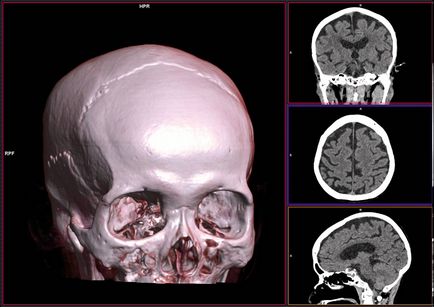

3D-s számítógépes tomográfia nem ritkák most!

Hol az MRI a gerinc, a belső szerveket, vagy fej nélkül, gyorsan a sorok? A válasz nyilvánvaló - magánklinikák. Legtöbbjük modern berendezések és képzett radiológus kell tisztázni előre megismerjék hivatalos honlapján és a vélemények.